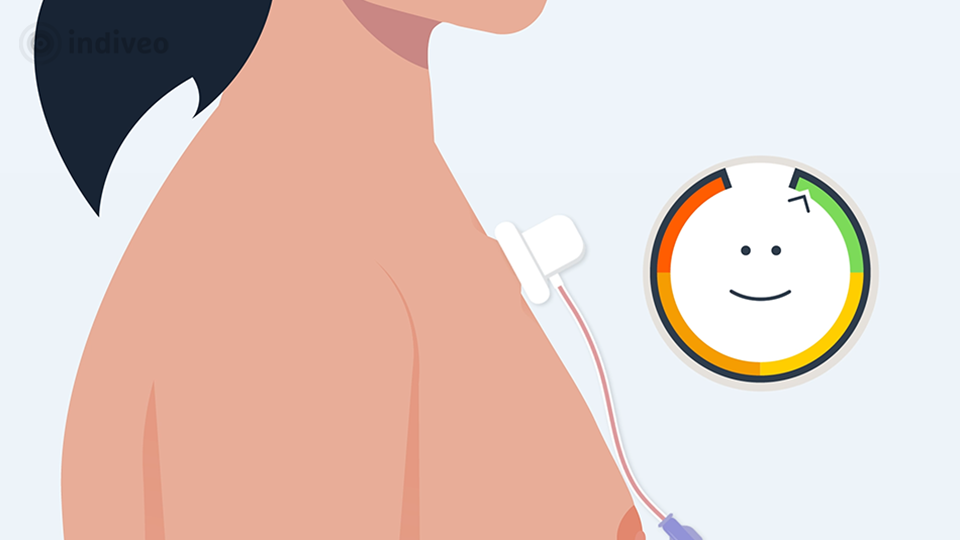

In deze Divi krijgt de patiënt uitleg over wat een port-a-cath is en waarom deze wordt geplaatst. De patiënt ziet dat dit een klein reservoir onder de huid is dat via een slangetje in een bloedvat ligt, waardoor medicijnen of vocht gemakkelijk toegediend kunnen worden en bloed kan worden afgenomen. Ook wordt uitgelegd hoe de plaatsing verloopt, hoe de port-a-cath gebruikt wordt tijdens behandelingen en waar de patiënt op moet letten in het dagelijks leven.